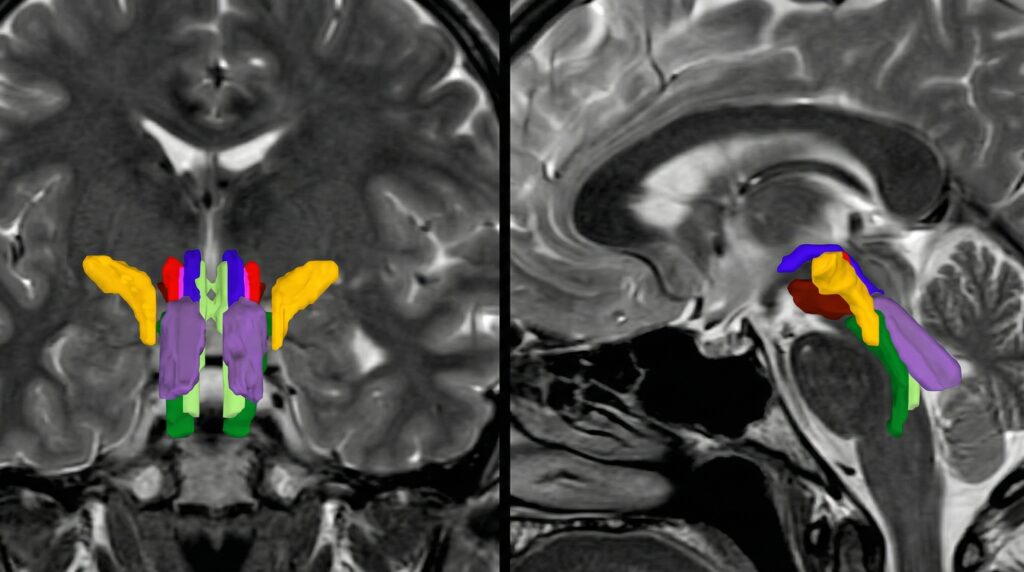

MIT: IA revoluciona análisis tronco encefálico con BSBT

El MIT ha desarrollado BSBT, una IA que segmenta haces de materia blanca…